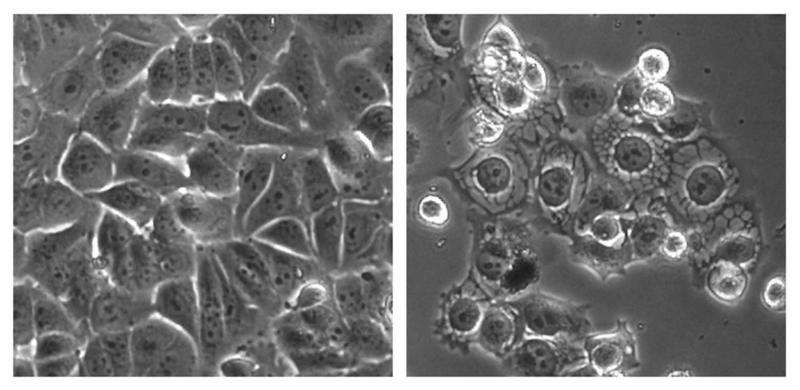

#Drug candidate kills #cancer cells through overstimulation http://bit.ly/1f3PMtF pic.twitter.com/zfNxjbbsVa